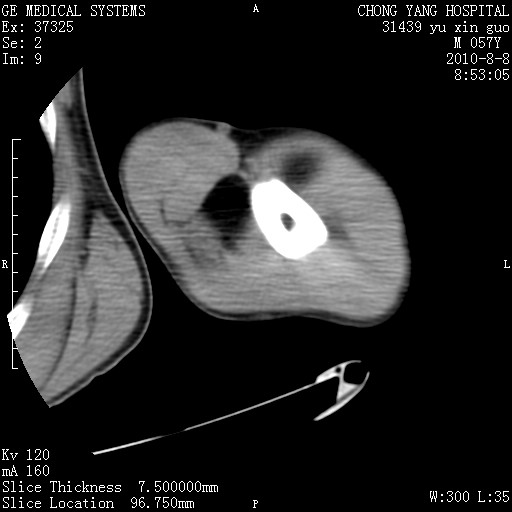

标题: CT28267:M57Y 上臂包块8年余。 [打印本页]

标题: CT28267:M57Y 上臂包块8年余。

典型脂肪瘤改变

上臂软组织内脂肪瘤。

包膜光滑、完整的脂肪密度肿块,支持脂肪瘤。

脂肪瘤。有ct值?